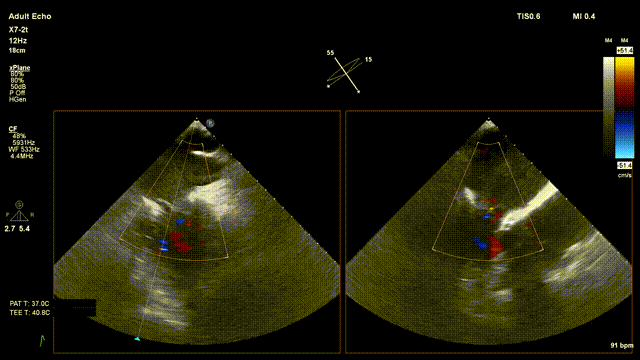

手术在单纯超声引导下完成,采用左侧第五肋间微创切口心尖入路,在食道探头引导下,清晰识别MitraFix®输送系统准确跨瓣,通过多平面超声引导下精准定位瓣膜方位,在双平面下精准定位瓣膜释放高度及保证系统的同轴性,最终将人工瓣膜准确释放于二尖瓣瓣环。

瓣膜释放后支架贴合牢固无瓣周漏,二尖瓣前向血流通畅, 左心室流出道通畅,流出道血流速度为0.53 m/s。顺利撤出输送系统,顺利完成手术。

术后超声评估:

术后无反流、左室流出道通畅